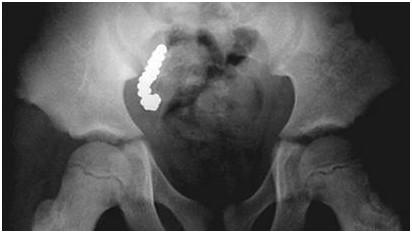

曾经有文献报道,一名澳大利亚8岁男童在玩家庭游戏时一共吞掉了57颗*弹铅**,这使得他的阑尾严重超负荷,因铅中毒被送入医院。X光显示他阑尾中装满了弹,最终阑尾也被割除。

男童的家人说他们经常用*弹铅**来射杀鹅,男孩和他的兄弟姐们们玩游戏的时候,轮流吃*弹铅**,让“它们消失”。这位小朋友一共吃了57颗*弹铅**,全部都跑到他的阑尾里面去了,正常的阑尾是4-5克,而由于慢性炎症的刺激,该男童的阑尾重达27.5克,是正常人的7倍。